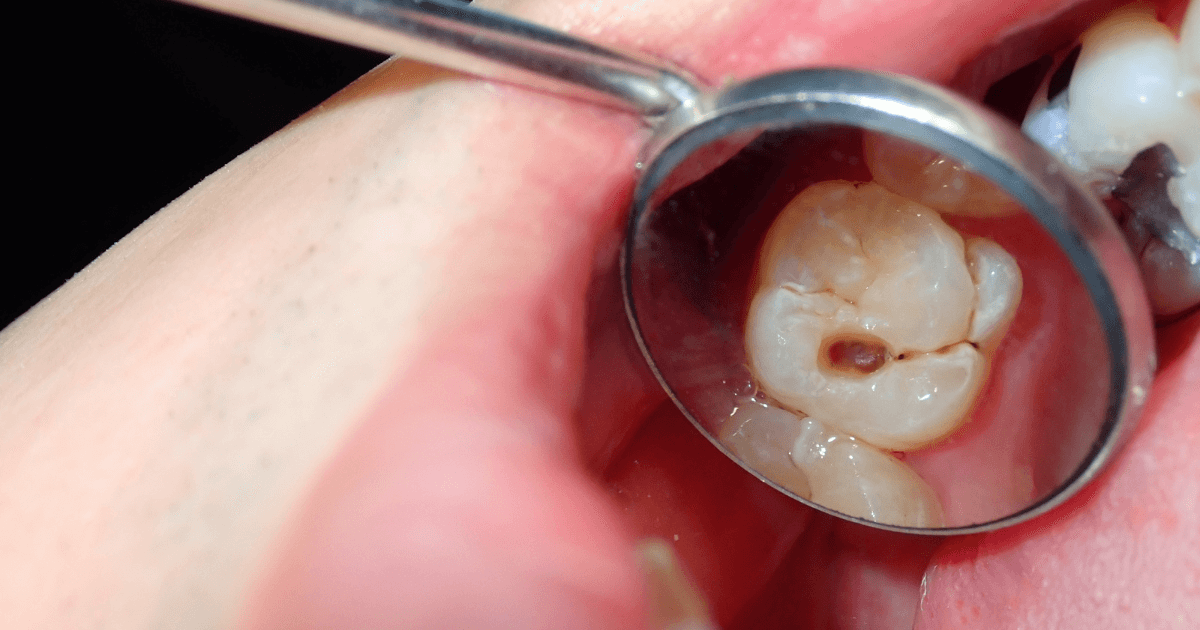

虫歯

初期の虫歯は表面の脱灰が中心です。刺激でしみやすい一方、刺激が去れば軽快しやすいのが特徴です。

穴が深くなると象牙質を越え、冷温や甘味で鋭い痛みが走るでしょう。食事や歯ブラシで違和感が続く場合は要注意です。

虫歯が進行すると夜間のズキズキや自発痛が出ます。歯髄が近い段階では、放置すると急に悪化しやすいでしょう。小さな欠けでも内部が広がる場合があります。早めの受診で処置範囲を小さくできる可能性があります。